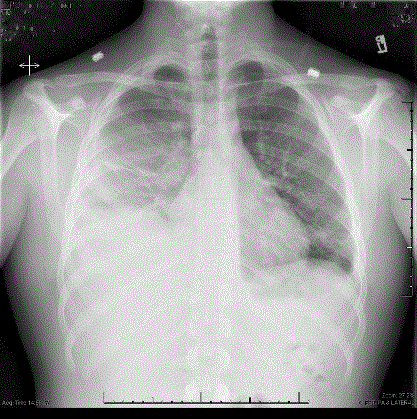

On admission, Clindamycin was started for the concern of a pulmonary abscess until gram stains on the blood cultures grew Gram Negative and Gram Positive Rods. The patient was then converted to Ceftazidime, to cover possible pseudomonas, and Vancomycin, for possible MRSA. Over the next day, he continued to have significant right sided chest pain and persistent leukocytosis, fevers, and oxygen requirement. A repeat CXR was obtained on his third day of admission which showed a large right sided pleural effusion (Figure 3). Blood cultures at this time came back positive for Fusobacterium necrophorum which raised immediate concern for Lemierre’s syndrome. He was restarted on IV Clindamycin and a CT larynx and chest was obtained, showing a possible non-loculated empyema, worsening infectious pneumonia, a clot in the left internal jugular vein, but no retropharyngeal abscess. (Figures 4 and 5). The Cardiothoracic surgery team was consulted and the patient went for right sided Video Assisted Total Decortication. They were able to peel off an exudate made up of fibrinous material with focal granulation tissue surrounding the lung and then drain the fluid. He had 3 chest tubes to drain fluid over the next few days, and was discharged on post-op day 5. On follow-up 2 weeks later, he was still on clindamycin and was feeling better, with no fevers and much improved breathing. During admission, the allergy/immunology team found he did not have a true penicillin allergy.

Figure 4. CT larynx

Figure 5. CT Neck